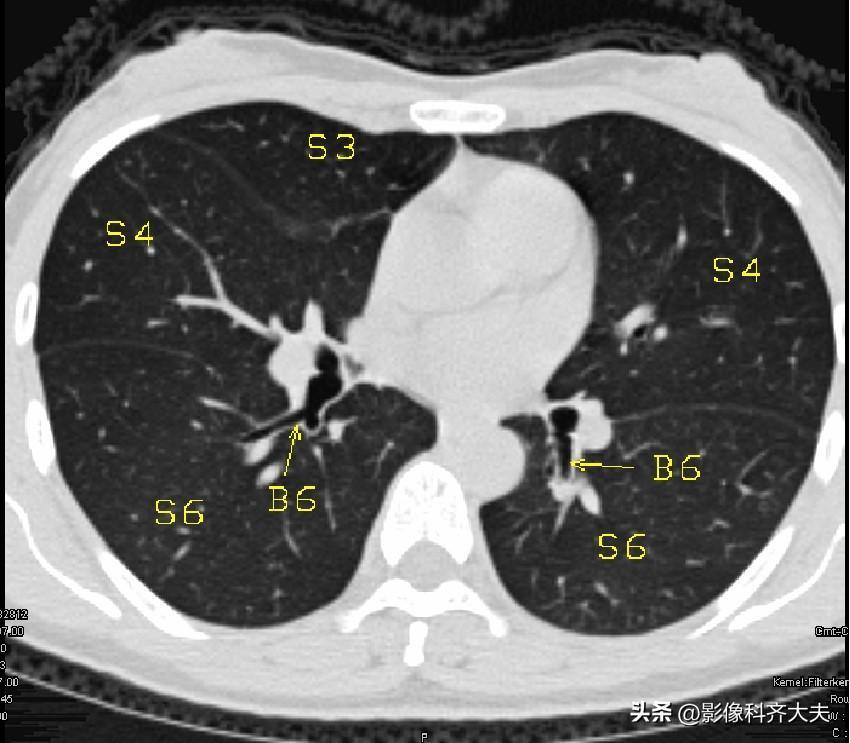

图12

▲B6:下叶背段支气管